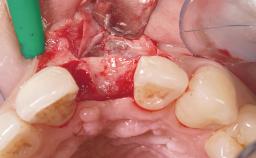

A 42-year-old female patient was referred to our clinic at the School of Dentistry of the University of São Paulo in November 2004, presenting a deficient restoration in the upper left central incisor. The clinical examination revealed no gingival retraction or any signs of gingival inflammation and, therefore, previous periodontal treatment was not considered. The patient presented a high lip line at full smile and a thin tissue biotype. This combination characterized a high-risk situation from an anatomic point of view, which required careful preoperative planning and cautious surgical execution.

Soft Tissue Grafting None

Soft Tissue Contour and Volume Ideal